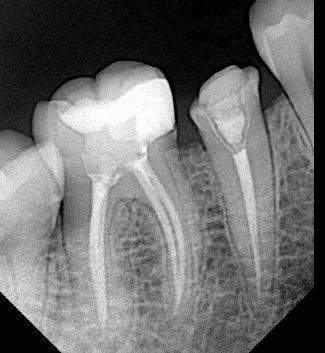

Pre-operative x ray

DME , look to the ribbond

After preparation

Final x ray